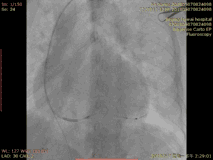

反复腋静脉造影,左侧腋静脉显影良好,植入临时起搏器,导丝进入下腔,开始寻找 CS,起初反复左前斜、右前斜都无法找到窦口。花了将近20min后,凑巧发现CS进入冠状静脉窦。普通鞘难以进入,反复尝试后长鞘进入CS,冠状窦十极退出CS。进行左前、正位造影,发现前侧血管机会不多,导线的四个极无法全部进入该侧支,更换PTCA导线进入偏侧壁分支,左室导线进入该分支。术后心电图示: QRS:130ms。

首先进行球囊冠状静脉造影,后考虑可能近段有血管未显影,于是在不打球囊的情况下再次造影,未发现合适血管,决定尝试近段血管,但猜测难度可能较大,导丝通过后,电极导线通过较难,决定尝试前侧静脉,导线仍然难以通过。再次造影,反复尝试尝试送入电极,靶静脉开口处扭曲,电极无法进入。使用鞘中鞘在侧枝开口作为支撑,在鞘中鞘支撑下,左室电极进入靶静脉,后顺利植入导线电极,尝试把电极送深处送,测试左室导线参数良好,阈值Tip端阈值1.5V/0.4ms,,5V无膈神经刺激。术后心电图:QRS 120ms。

冠状窦口寻找顺利,进行造影,进行CS造影是发现远端两支分支以及一支后静脉的分支,应该如何选择?是否需要鞘中鞘?我们根据血管走行选择的是中间的一支血管,并使用鞘中鞘。鞘中鞘指引完成靶静脉到位,而后发现有膈肌夺获,于是换另外一支分支血管。同样鞘中鞘指引完成靶静脉,送入电极。但是撤鞘管后发现电极移位,使用Stylet复位深插,电极回复合适位置。

造影结果显示其分支血管较少,在后侧有一根较粗的后侧静脉可作为靶静脉,靶静脉有导向侧壁的细小分支,靶静脉开口离冠状窦口较近,且有点扭曲。靶血管条件不佳。我们考虑四极电极S形态或成角的四极电极,4298四极电极,四个极性都有激素覆盖,LV2-LV3短间距,减少膈肌刺激,可兼容鞘中鞘6248。靶静脉开口离冠状窦口较近,且有点扭曲利用6248可以提供更好的支撑力。在鞘中鞘6248的支撑下,电极顺利植入。16个起搏向量阈值阻抗一键测试,配合无线遥测,全程只需2-3分钟。